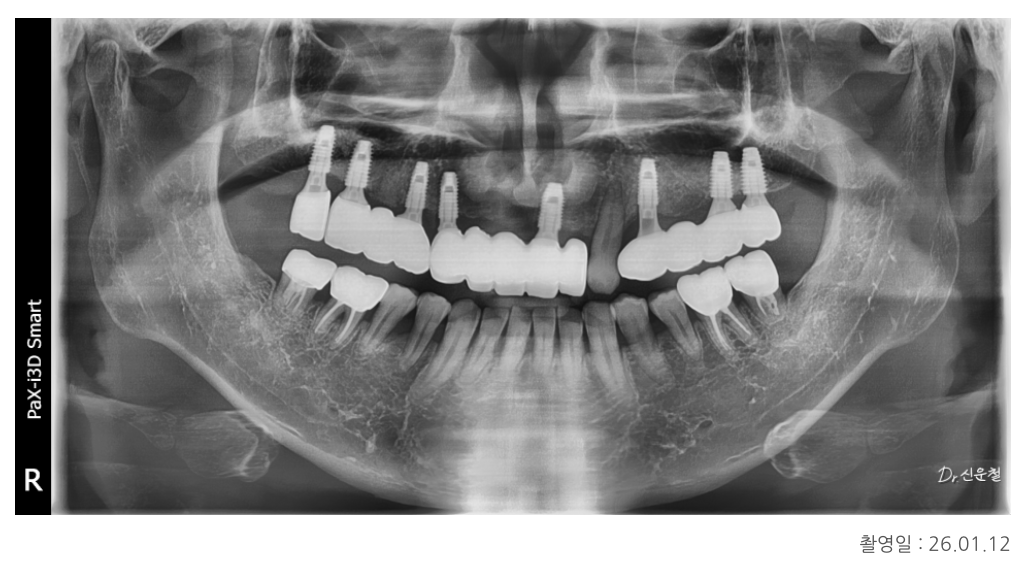

앞니는 ‘치아 + 잇몸’을 함께 고려

임플란트 식립 후 보철 단계에서

특히 앞니는 더 신중하게 접근했습니다.

치조골이 전반적으로 내려간 상태였기 때문에

단순히 치아 색 보철물만 사용하면

앞니가 부자연스럽게 길어 보일 수 있었습니다.

그래서

치아 부분은 치아 색으로

잇몸이 있어야 할 위치에는 잇몸처럼 보이는 핑크 보철을 함께 표현해

자연스러운 인상을 만들었습니다.

“웃을 때 입을 가리지 않게 됐어요”

치료가 마무리된 후

환자분께서 이런 말씀을 하셨습니다.

“웃을 때 입을 가릴 필요가 없어졌어요.”